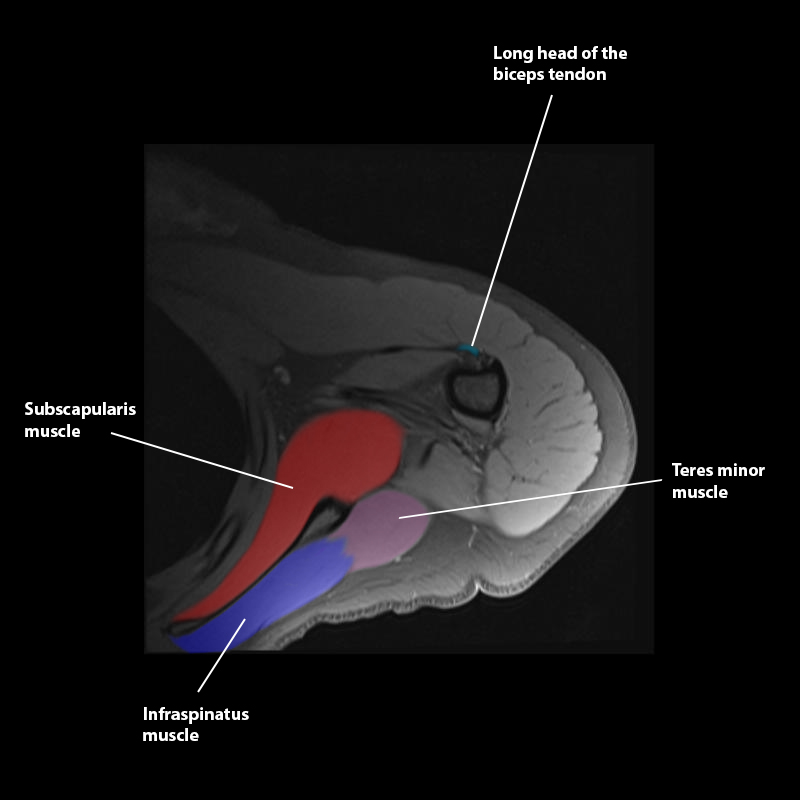

Shoulder MRI Anatomy